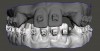

Digital technology is not only great for diagnosis and treatment planning, it also allows that plan to be easily integrated into the restorative workflow. This is a distinct advantage over conventional workflows, especially in esthetic cases when it is critical to meet patient expectations. An illustration of this is a patient presenting with a desire to address his chipped maxillary incisors to make them more esthetic (Figure 1). Using digital photography, a retracted photograph of the patient's teeth was imported into smile-design software, which provided a quick and simple means of establishing a symmetrical restorative design for the patient (Figure 2). Within the same software, the proposed restorations were then overlaid on a full-face smiling photograph (Figure 3), and the patient was able to compare before-and-after photographs (Figure 4). The patient approved of the proposal, which was then imported into CAD software to facilitate fabrication of the final restorations based on the smile-design proposal (Figure 5).

Fig 1. Retracted preoperative view of chipped maxillary incisors.

Figure 1